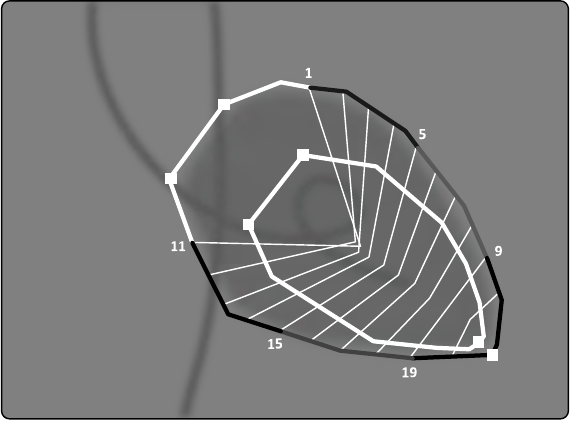

10.5.4 Zadanie etapu końcowo-rozkurczowego (ED)...................................................... 171

10.5.5 Zadanie fazy końcowo-skurczowej (ES)................................................................ 173

10.5.6 Edytowanie konturu............................................................................................. 175